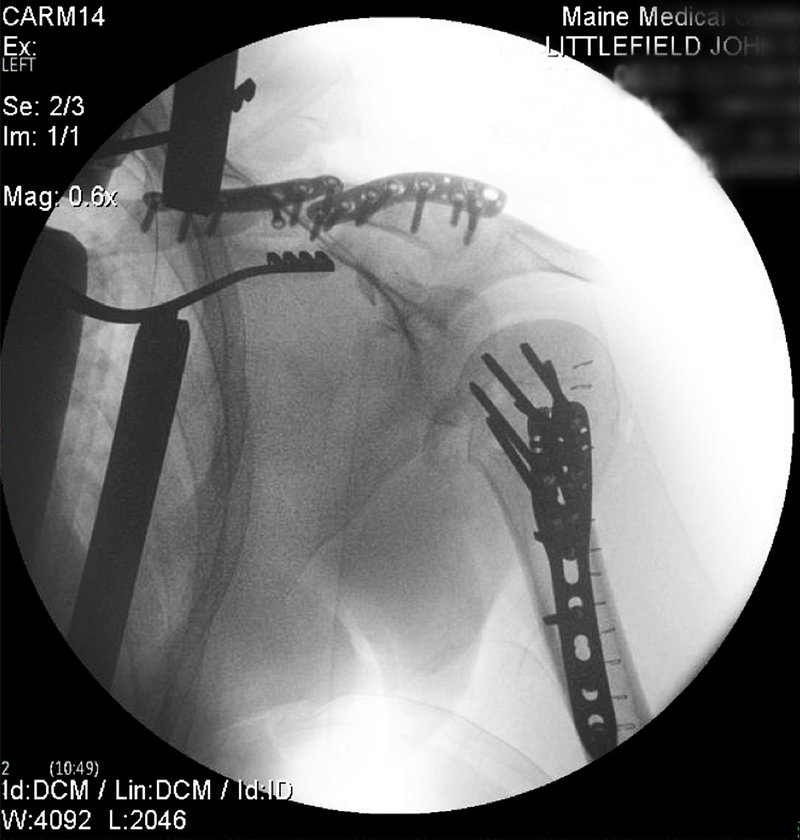

Those injuries turned out to be a broken humerus, clavicle and scapula, broken neck vertebrae and ribs, and a collapsed lung. Littlefield would undergo two surgeries, involving stainless steel plates and screws, and spend 10 days in the hospital. The last of the metal pieces was removed two months ago.